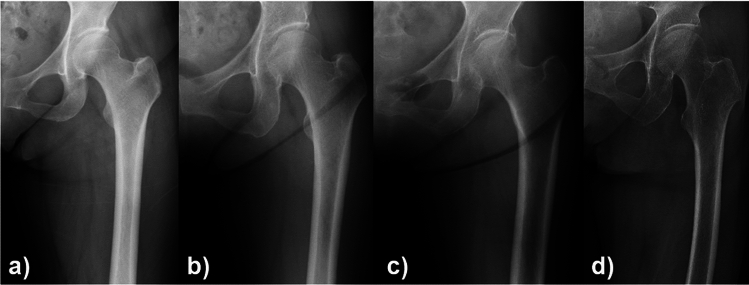

Fifteen orthopedic surgeons, including five board-certified surgeons (staff surgeons) and 10 residents (less than four years of experience in orthopaedics), participated in this study. First, a surgeon who did not participate in the X-ray assessment selected the anteroposterior hip X-ray and created the material for assessment. The surgeon was blinded with regard to the operated side and patient demographics (e.g., age and hip disease) in order to avoid bias (Fig. 1a–d). Then, each surgeon visually inspected the hip X-rays and scored the suspicion of osteoporosis on a scale of 1–4 (1: very unlikely (Fig. 1a), 2: unlikely (Fig. 1b), 3: suspicious (Fig. 1c), and 4: very suspicious (Fig. 1d)) for each case (pred-score). The average pred-score of all surgeons for each case was also calculated (ave.pred-score). Interobserver and intraobserver agreement was assessed because visual inspection is subjective. Specifically, eight surgeons (four staff surgeons and four residents) visually reassessed the hip X-rays of 100 patients with an interval of more than two weeks.

Fig. 1.

Examples of four X-rays used to classify osteoporosis likelihood. The ave.pred-score of 15 surgeons for these cases were a 1.1, b 2.0, c 2.9, and d 3.9